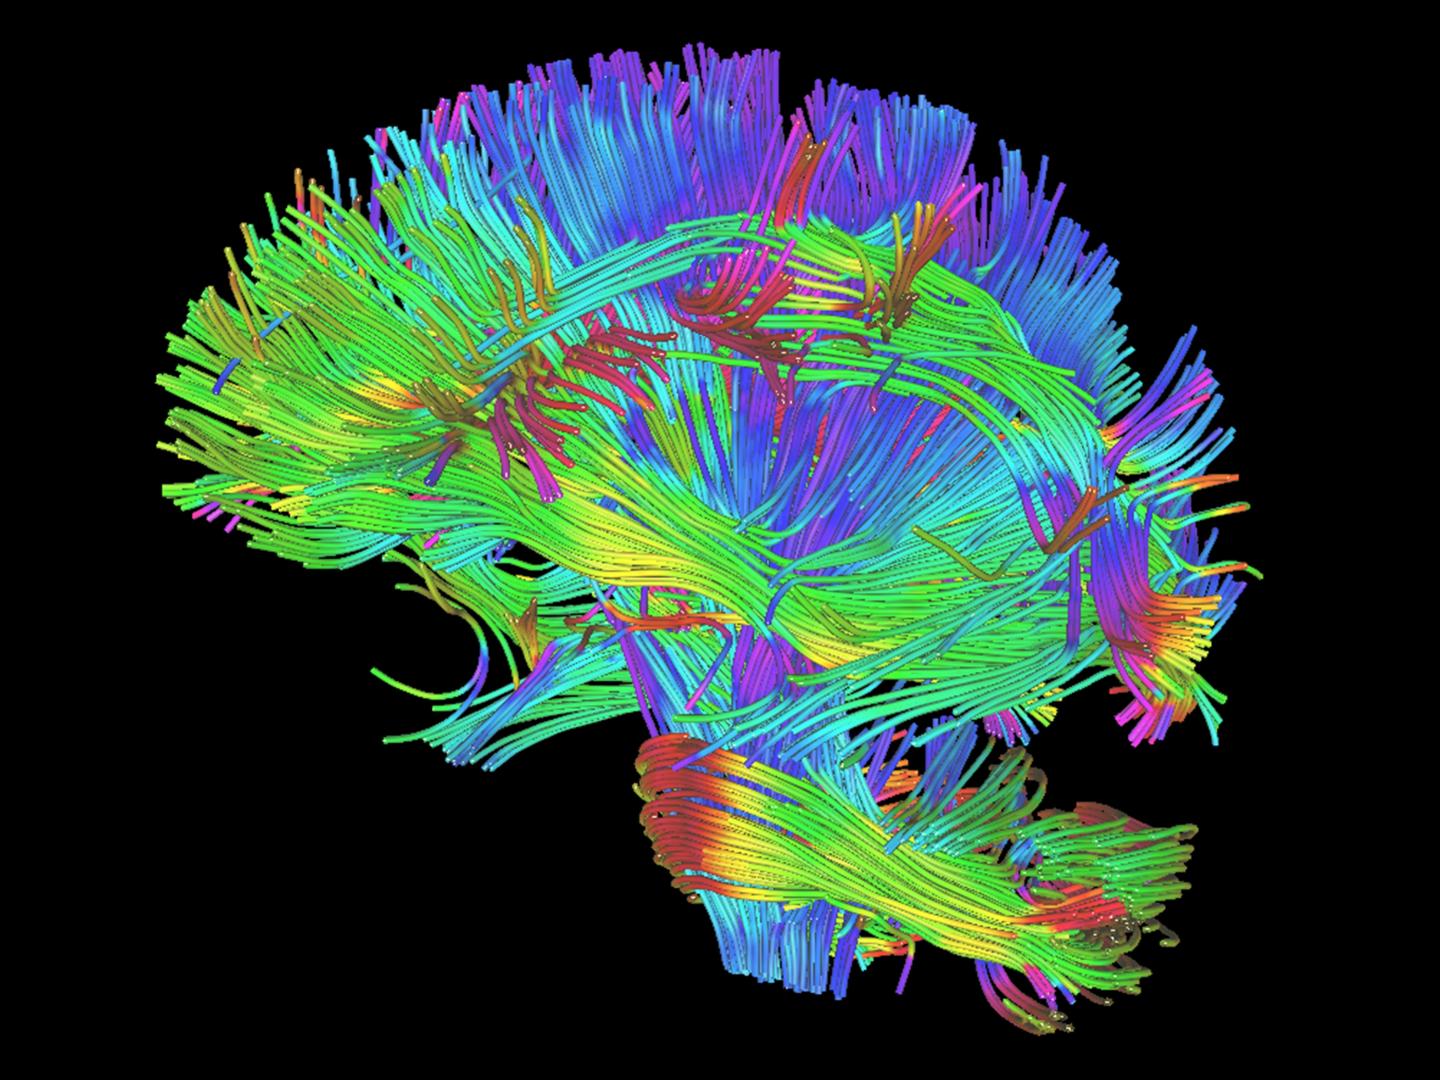

In the study, each player underwent pre- and post-season imaging: a specialized MRI scan, from which diffusion tensor imaging (DTI) and diffusion kurtosis imaging (DKI) data were extracted to measure the brain's white matter integrity, and a magnetoencephalography (MEG) scan, which records and analyzes the magnetic fields produced by brain waves. Diffusion imaging can measure the structural white matter changes in the brain, and MEG assesses changes in function.

"MEG can be used to measure delta waves in the brain, which are a type of distress signal," Dr. Davenport said. "Delta waves represent slow wave activity that increases after brain injuries. The delta waves we saw came from the surface of the brain, while diffusion imaging is a measure of the white matter deeper in the brain."

The research team calculated the change in imaging metrics between the pre- and post-season imaging exams. They measured abnormalities observed on diffusion imaging and abnormally increased delta wave activity on MEG. The imaging results were then combined with player-specific impact data from the HITS. None of the 24 players were diagnosed with a concussion during the study.

Players with greater head impact exposure had the greatest change in diffusion imaging and MEG metrics.

"Change in diffusion imaging metrics correlated most to linear acceleration, similar to the impact of a car crash," Dr. Davenport said. "MEG changes correlated most to rotational impact, similar to a boxer's punch. These results demonstrate that you need both imaging metrics to assess impact exposure because they correlate with very different biomechanical processes."